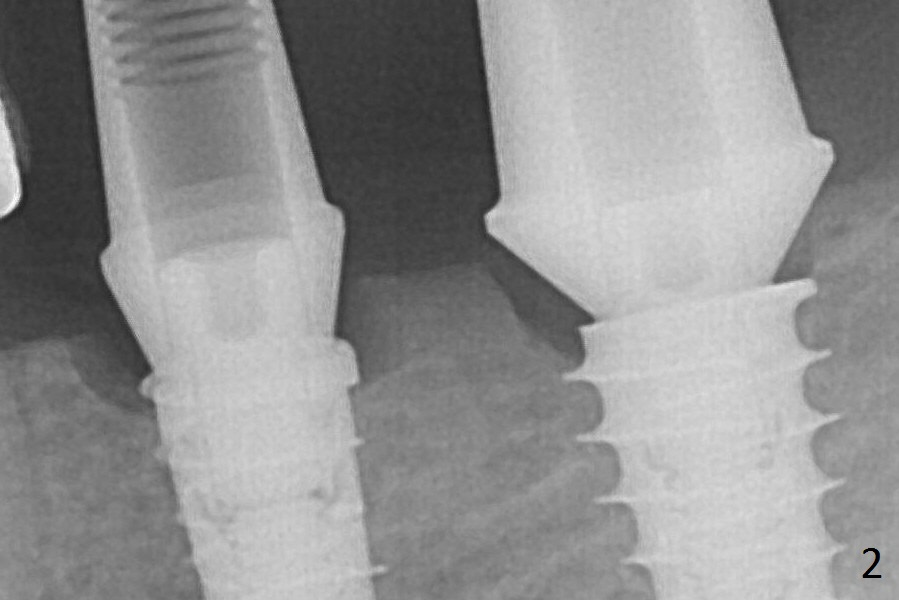

After Magic Drills (3.3 and 4.3 mm at #19 and 18, respectively), 4x11 and 5x9 mm IBS implants are placed with insertion torque >35 Ncm with immediate placement of pair abutments (4.5x5.7(2) and 6.5x4(2) mm, Fig.2). In fact these sites are converted to a premolar and a 1st molar (because narrow ridge at #19). Following GBR and suturing, periodontal dressing is applied around the abutments for increased retention. The regional ridge reduction makes Marking Bur unnecessary (because of flat ridge top and the soft bone in this case) and more importantly there is no thread exposure upon implant placement. The trimmed site (concavity) is favorable for bone graft and membrane placement.